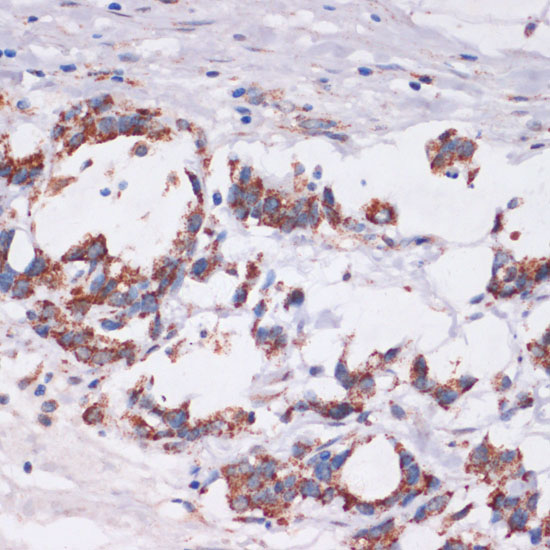

Immunohistochemistry of paraffin-embedded human gastric cancer using DVL2 at dilution of 1:100 (40x lens).